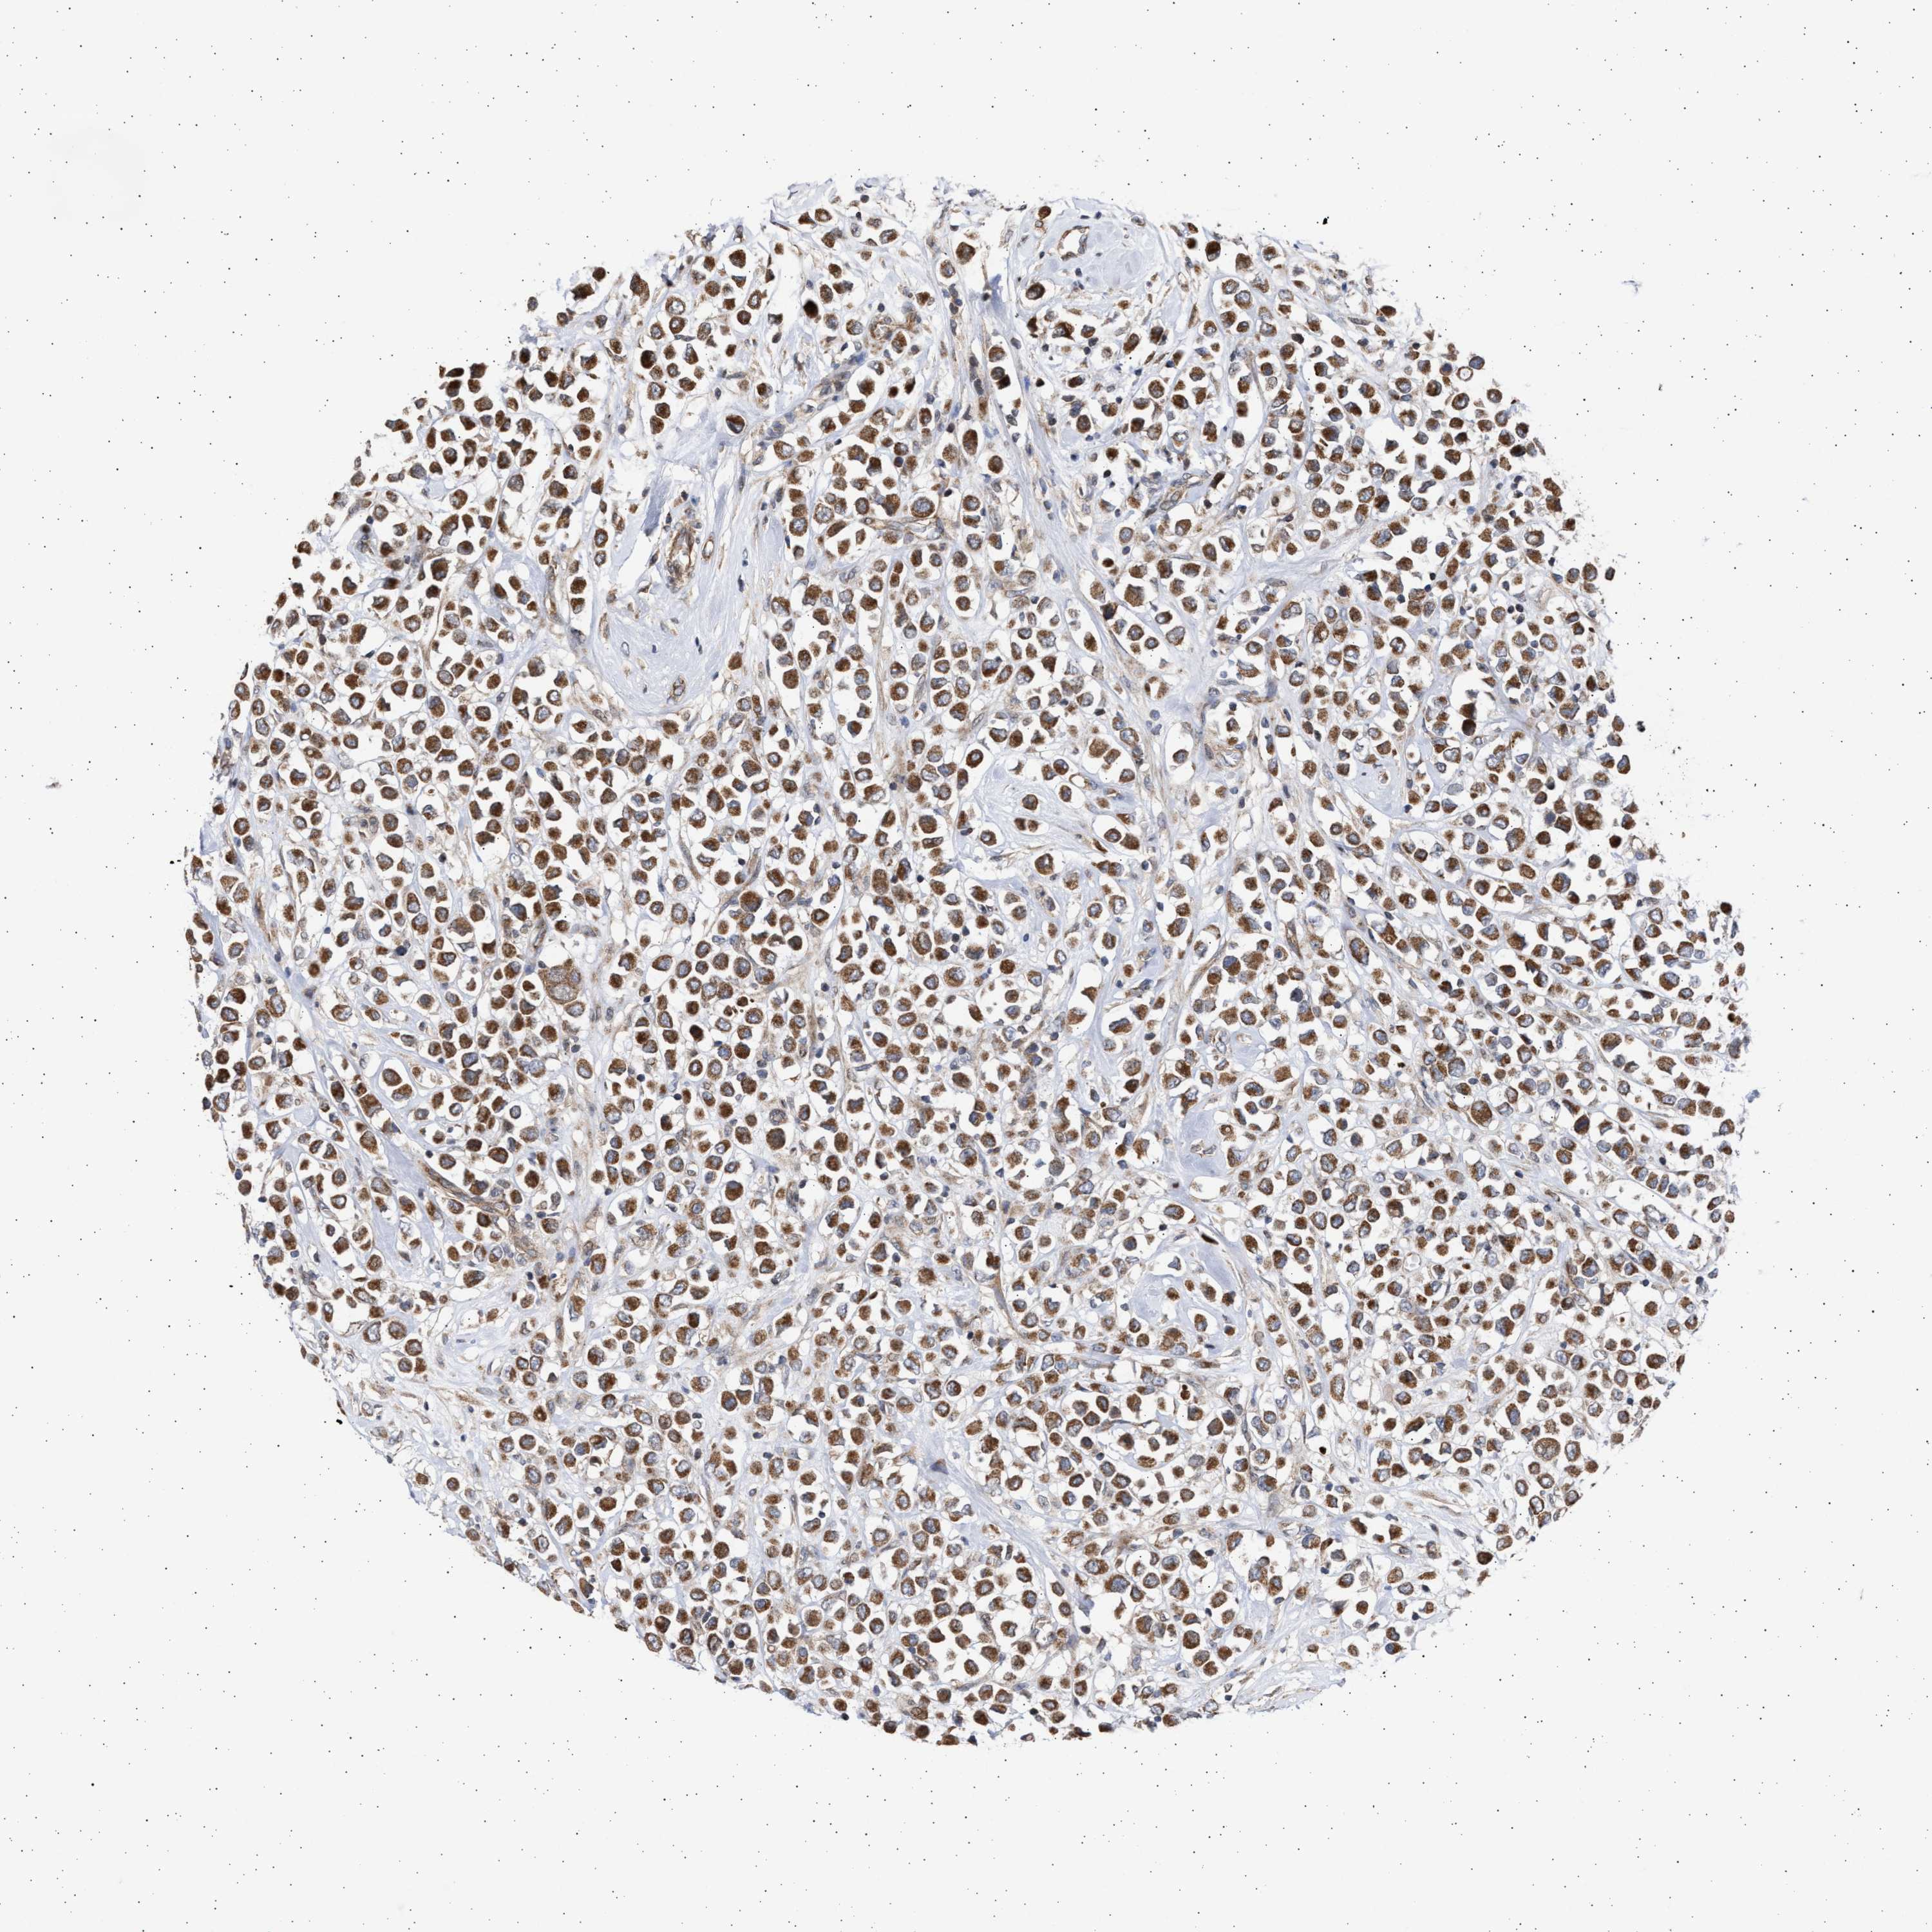

CANCER BREAST CANCER Show tissue menu

BRCA TCGA BRCA VALIDATION PROTEIN EXPRESSION